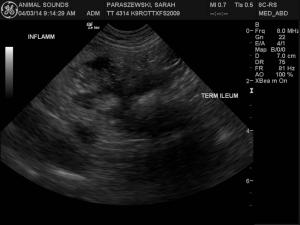

Scan revealed complex large mass like structure adjacent to ileo-colic-cecal junction, no obstrution or free air. No other significant findings.

• In the first video for the orginal scan you can see the thickened terminal ielum dorsal and caudal (at 5:00 on the image) to the mass

• Second video show transverse of same area